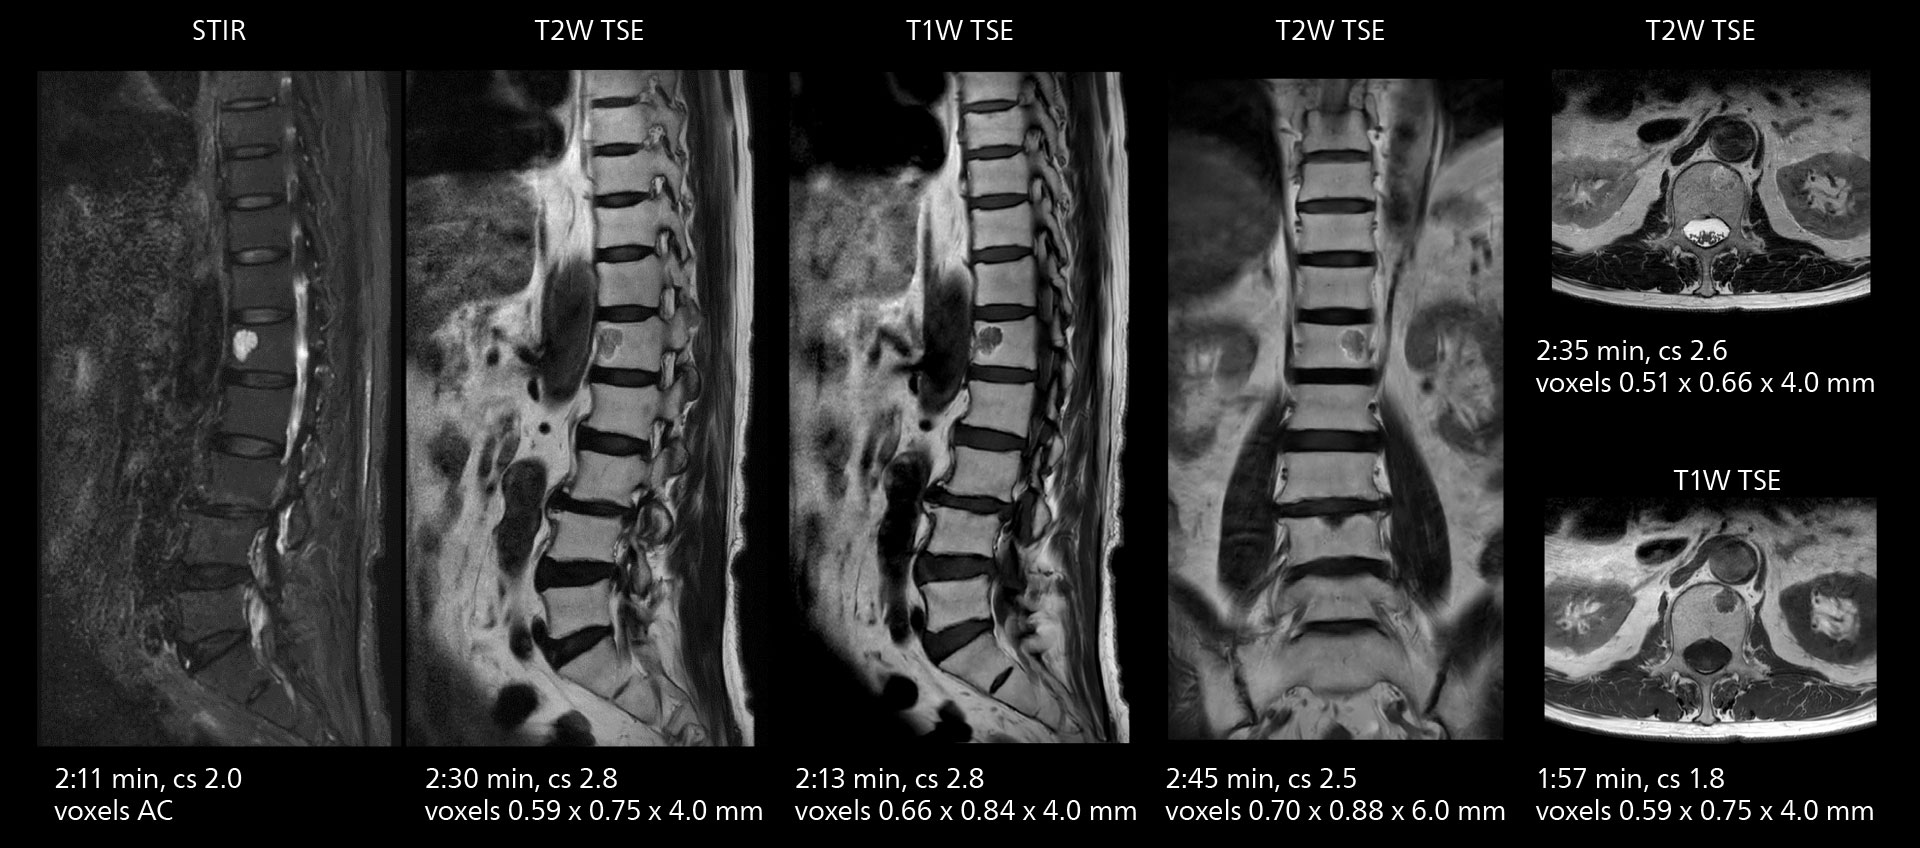

Examples of prostate imaging showing faster scan times and improved resolution illustrate the power of SmartPath to Elition X in this case of prostate cancer with PI-RADS score 4.